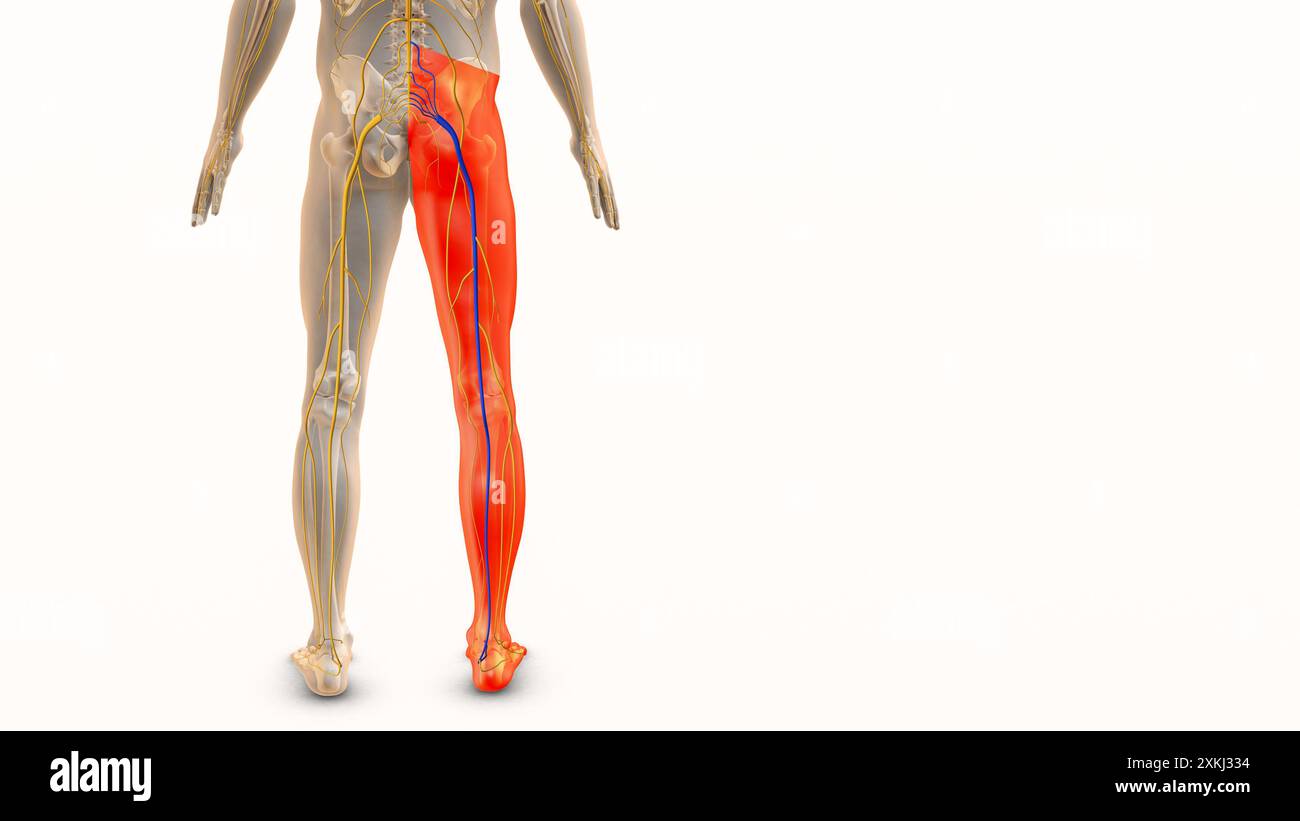

Medizinisches Konzept für Ischiasnervenbeschwerden Stockfotohttps://www.alamy.de/image-license-details/?v=1https://www.alamy.de/medizinisches-konzept-fur-ischiasnervenbeschwerden-image614438920.html

Medizinisches Konzept für Ischiasnervenbeschwerden Stockfotohttps://www.alamy.de/image-license-details/?v=1https://www.alamy.de/medizinisches-konzept-fur-ischiasnervenbeschwerden-image614438920.htmlRF2XKJ334–Medizinisches Konzept für Ischiasnervenbeschwerden